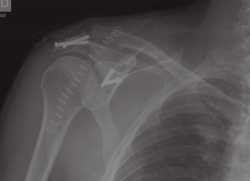

La radiología simple, única proyección anteroposterior, a su llegada a urgencias, muestra una fractura de la cavidad glenoidea que parece incluir la apófisis coracoides y una fractura del acromion sin desplazamiento significativo (Figura 1).

Figura 1. Radiografía anteroposterior tomada el día del traumatismo. Obsérvese la fractura de glenoides y del acromion.